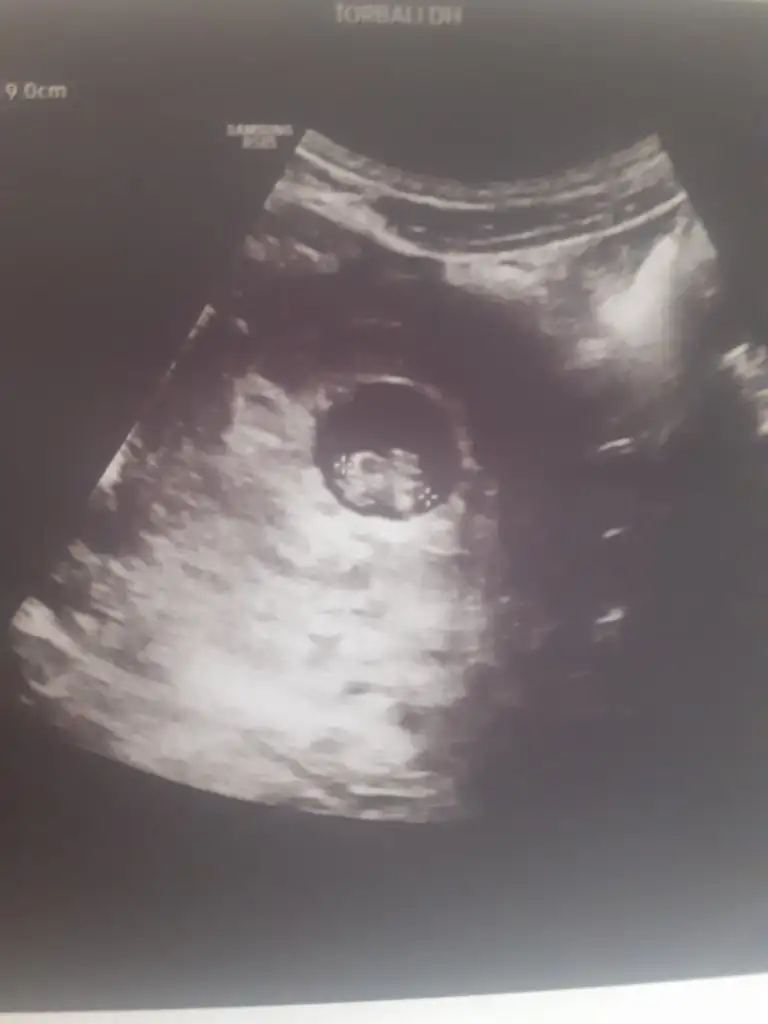

bebek göremedim yolk saç var canım maalesef yorum yapamam5+5 burada banada bakar mısın